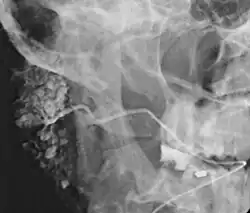

Sjalografia[1][a] – kontrastowe badanie rentgenowskie przewodów i miąższu ślinianek.

Zapisem tego badania jest tak zwany sjalogram[2][b], dzięki któremu lekarz ma możliwość dokładnego i wyraźnego obejrzenia układu śliniankowych przewodów wyprowadzających oraz określenia rodzaju, lokalizacji i rozległości zmian patologicznych.